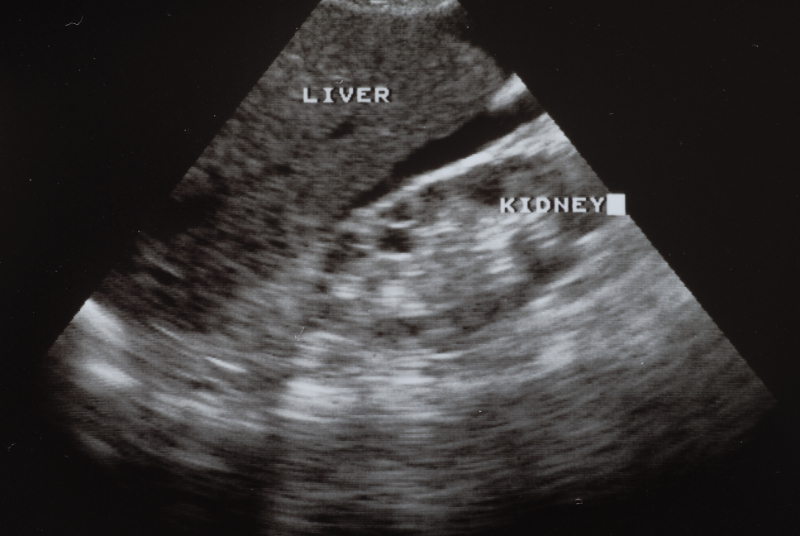

Focused Assessment with Sonography for Trauma (FAST) is an essential part of the primary circulation survey for unstable patients, in whom it often determines management. FAST is used primarily to detect pericardial and intraperitoneal blood, and it is more accurate than any physical examination finding for detecting signs of intra-abdominal injury. (Image 3)

Image 3:Ultrasound

Licensed from Shutterstock

(Fluid volumes of 200 mL have been reported to be detectable via ultrasound. Findings on a FAST examination must be placed in the appropriate clinical context because the detected fluid may be blood, ascites, urine, or peritoneal dialysate.)

FAST can be delayed until the secondary survey in hemodynamically stable patients and is ideally performed by a second operator while the remainder of the secondary survey is completed.

The accuracy and role of FAST may be more limited in patients with significant pelvic fractures because it is less sensitive for detecting pelvic bleeding and cannot differentiate between blood and urine. Retroperitoneal bleeding is also not reliably visualized with ultrasound. FAST is less sensitive for injury in penetrating trauma than blunt trauma, and the results of ultrasound examinations in penetrating trauma patients, particularly negative results, must be interpreted with caution.

The Extended FAST (E-FAST) includes examinations of the thoracic cavity looking for pneumothoraces. Preliminary studies suggest the sensitivity of E-FAST is better than plain x-ray for this injury.